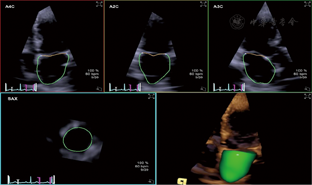

eSie LVA软件将左房全容积图像切分显示为心尖四腔、两腔、三腔和短轴基底、中间和房顶切面,调整取样线清楚显示图像。设定左房舒张末(LAED)和收缩末(LAES)为左房容积最大(LAVmax)和最小处(LAVmin),LAES为时间起点。LAED、LAES帧手动标记房顶和二尖瓣环侧壁、房间隔三点,软件完成心房内膜边界追踪,逐帧观察,必要时手动调整边界(左心耳和肺静脉开口排除在外)(图1),显示左房容积曲线。

3D–mechanics软件将左房全容积图像切分显示为多切面(同前),软件默认将左房壁按左室16节段划分。根据解剖结构特点我们将左房划分为基底(Basal)、中间(Middle)、房顶(Roof)三部分(分别对应16节段基底、中间和心尖部)(图2),调整图像使三部分划分更接近其空间构型。LAES为时间起点,LAED、LAES帧手动描记左房内膜边界后软件自动追踪其运动轨迹,逐帧观察调整。左房三部分形变以三维速度向量(VVI)模式和应变曲线显示(图2),调整显示模式和时间间期,计算获取参数。主要参数:左房基底、中间、房顶部和整体(Global)心室收缩期长轴峰值应变(LSs%)和心房收缩前长轴峰值应变(LSa%),分别记为BLSs、MLSs、RLSs、GLSs和BLSa、MLSa、RLSa、GLSa(图2)。整体应变为三部分应变均值。在3D–STE基础上,参考既往研究[8]引入左房僵硬指数(LA stiffness index),其定义为E/Ea与GLSs%比值,数值越大表明左房僵硬度越高,顺应性越低。